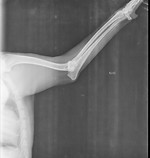

Exames de Imagem

clique para ampliar | em atualização

Displasia Cotovelo